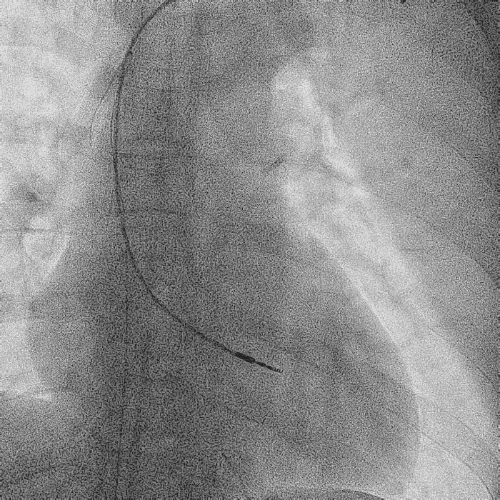

在心房和心室电极成功拔除后,患者立刻感觉“眼前一亮”,颜面肿胀感缓解,此时颈静脉怒张相比术前也明显缓解。再次复查上腔静脉造影,狭窄明显减轻,无需再使用上腔静脉扩张球囊进行扩张。

电极拔除后

颈静脉怒张

明显缓解

上腔静脉狭窄